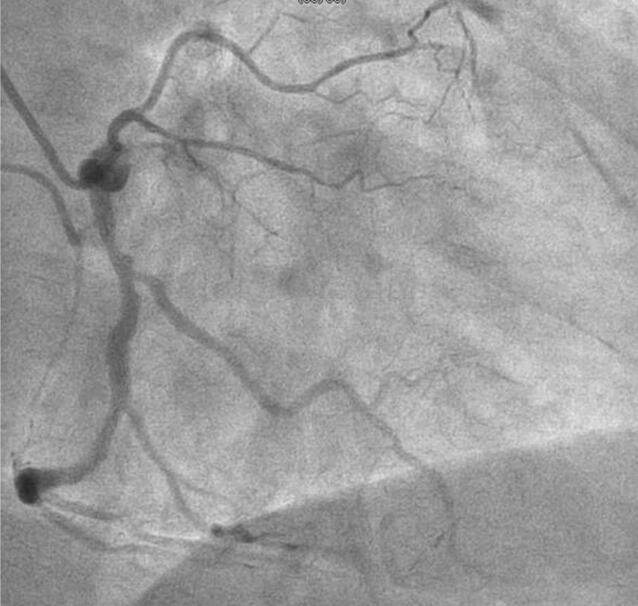

57岁男性突发胸骨后持续性疼痛,他怎么了?|

1200x1101 - 242KB - JPEG